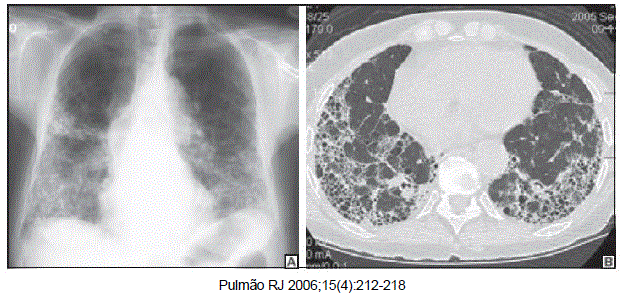

Mulher de 69 anos de idade, natural e procedente de São Paulo é dentista. Tabagista de 20 maços-ano, apresenta dispneia e tosse seca há 2 anos, sem outras queixas. No exame clínico apresenta saturação de oxigênio de 90% em ar ambiente e estertores em velcro bilaterais, sendo o restante do exame clínico normal. A radiografia e tomografia de tórax estão a seguir. A espirometria mostra VEF1 e CVF diminuídos com relação VEF1/CVF preservada.